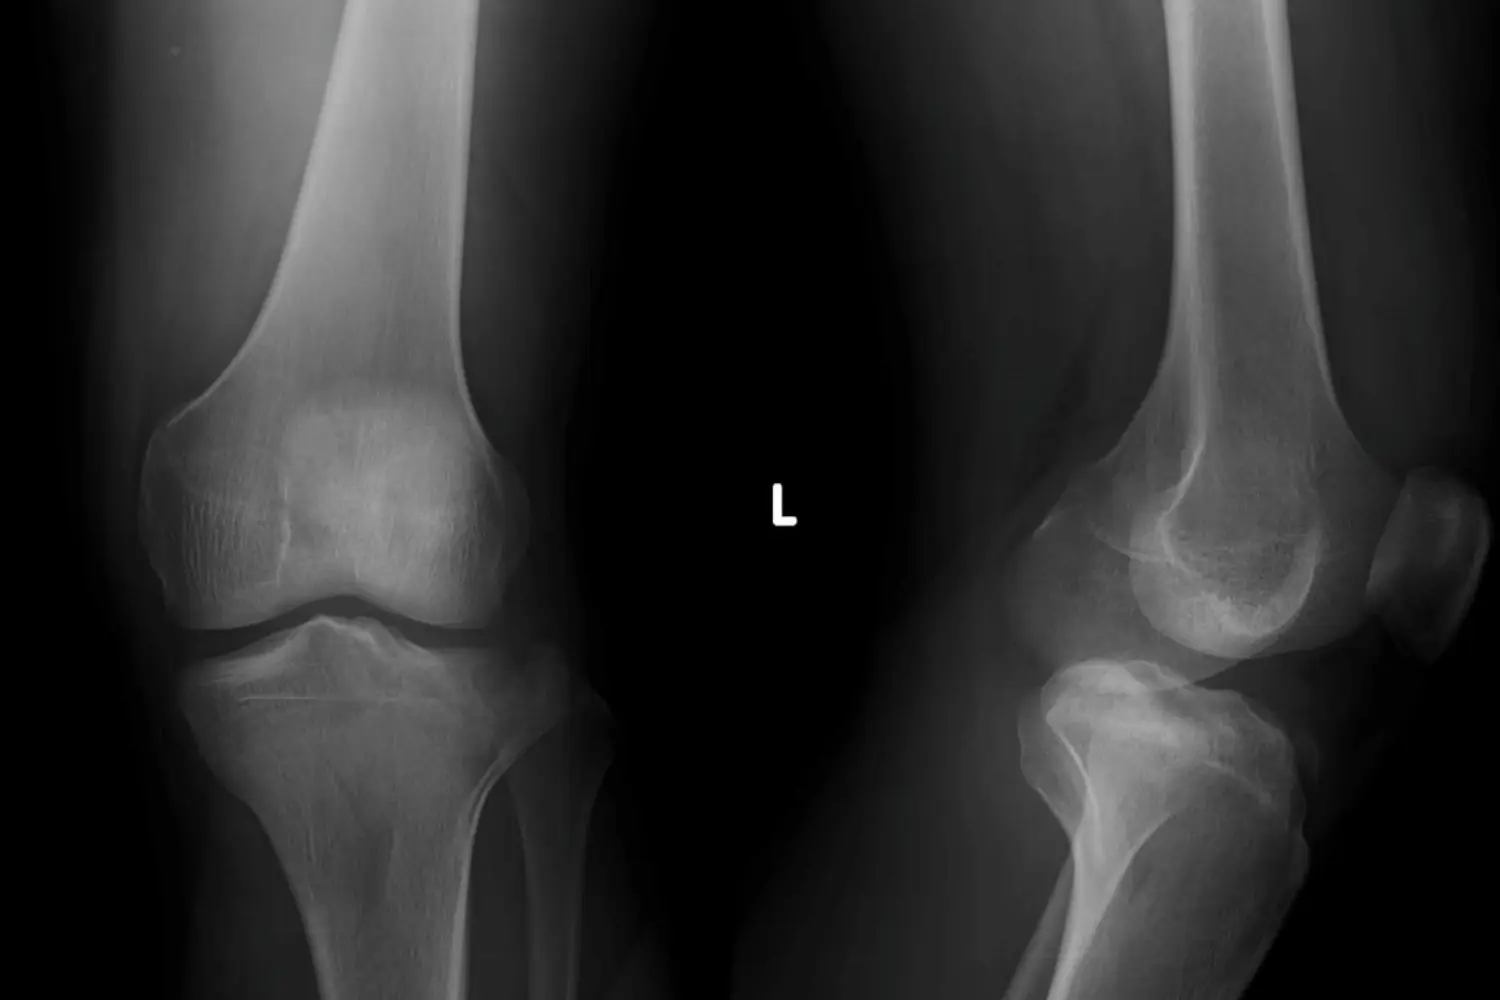

Knee Replacement Surgery in Coimbatore – Advanced Joint Care